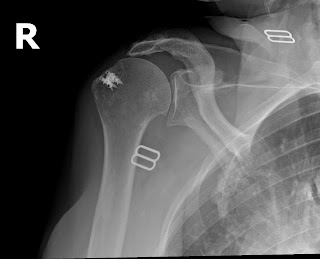

Each patient has had an arthroscopic rotator cuff repair by another surgeon. The first set of films demonstrate that the metal anchors have pulled out of the very soft bone and as a result the tendon has retorn after a rotator cuff repair. This failure was within the first year. This patient was in therapy for many months and could never lift her arm after the repair. Her pain was considerable and she became very unhappy with the situation and eventually came to me for help. A simple x-rays tells the whole story. No MRI needed here. The only set of post operative x-rays done were those done in my office about a year after surgery.

The fact that the anchors are now out of the bone, floating in the joint, indicate that this mechanism of failure. Rotator cuff tendon quality also affects the success of a tendon repair. Poor quality tendon in more likely to retear. Larger tears involving more than one of the 4 rotator cuff tendons will have a higher failure rate as well. Patients over 65 years of age and chronic tendon tears will also have higher rates of failure.

Notice the metal anchors above that seem to be floating in the joint. This foreign body in the joint is very painful. I did surgery on the above patient to remove the anchors arthroscopically. Her pain improved, but her function never recovered. Although I thought she would have done well with a reverse total shoulder replacement, she said that she had enough surgery. I advised her about the limits of surgery under these conditions and, after surgery, she was happy that her pain was improved.